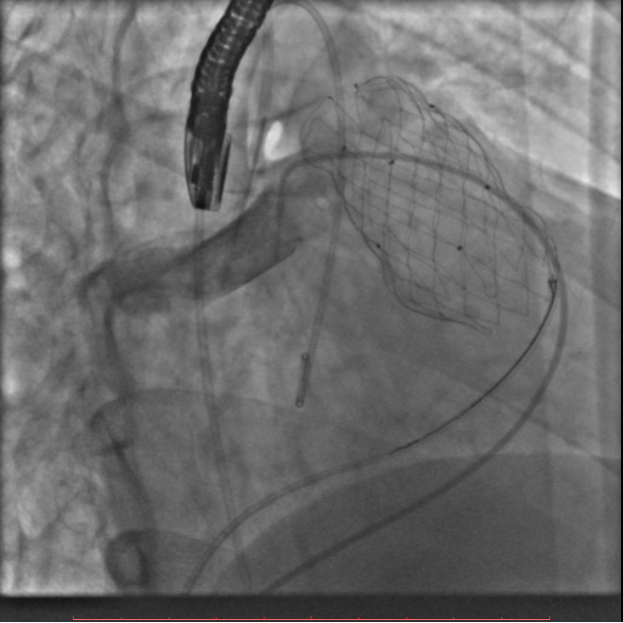

术中测量患者基础主动脉、肺动脉、右心室压力分别为111/58mmHg、31/4/13mmHg、34/1/6mmHg,通过肺动脉造影,术中测量球囊内径为32mm(见图二),选择36-25mm VENUS-P肺动脉瓣膜,在肺动脉造影指引下逐步打开瓣膜。考虑到患者肺动脉分叉较短,存在瓣膜释放后移位风险,故选择高位释放法(图三)。但释放瓣膜后造影提示右肺动脉开口局部被阻挡(图四),复测患者主肺动脉、左肺动脉、右肺动脉压力分别为57/13/25mmHg、55/12/24mmHg、27/7/14mmHg。

图三:考虑到患者肺动脉分叉较短,选择高位释放法

图四:主肺动脉造影及选择性右肺动脉造影提示右肺动脉开口局部被阻挡